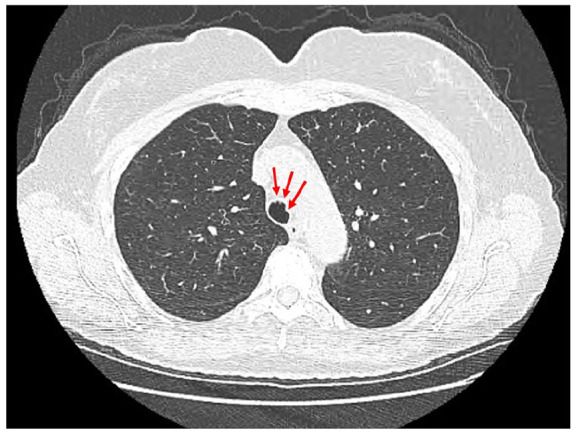

气管支气管骨性软骨病变(TPO)是一种罕见的良性疾病,其特征是存在粘膜下软骨和骨性结节,突出到气管支气管管腔的前壁和侧壁,保留后膜壁。这些结节是偶然发现的影像学和支气管镜检查不相关的呼吸道症状。确切的发病机制尚不清楚,提出了各种假说。最广为接受的说法是慢性炎症导致气管支气管粘膜下层软骨和骨性化生。TPO是罕见的,由于诊断的偶然性,患病率进一步被低估。临床上,患者可能无症状,也可能有非特异性症状,如慢性咳嗽、呼吸困难和反复呼吸道感染。在气管支气管管腔偶然发现结节时,对诊断产生怀疑。诊断是通过支气管镜观察保留后壁的特征性结节病变建立的,可以通过组织病理学检查显示粘膜下软骨形成和骨化来证实。管理一般是保守的,重点是症状缓解和治疗感染。严重的气道阻塞病例可能需要进行先进的支气管镜检查或手术干预。尽管它是良性的,但TPO可以模仿其他严重的气管疾病。了解这种情况对于准确诊断和适当管理至关重要。我们报告一个65岁无症状慢性吸烟者的病例,他在胸部影像学上发现气管结节。支气管镜检查与TPO一致,组织病理学证实了诊断。

Tracheobronchopathia osteochondroplastica (TPO) is a rare, benign condition characterized by the presence of submucosal cartilaginous and osseous nodules protruding into the anterior and lateral walls of the tracheobronchial lumen, sparing the posterior membranous wall. These nodules are incidentally discovered on imaging and bronchoscopy performed for unrelated respiratory symptoms. The exact etiopathogenesis is unclear, with various hypotheses proposed. The most widely accepted one is that chronic inflammation leads to cartilaginous and osseous metaplasia of the tracheobronchial submucosa. TPO is rare, with the prevalence further underestimated due to the incidental nature of the diagnosis. Clinically, patients may be asymptomatic or can have nonspecific symptoms such as chronic cough, dyspnea, and recurrent respiratory infections. Suspicion of the diagnosis arises upon incidental identification of nodules in the tracheobronchial lumen. Diagnosis is established through bronchoscopic visualization of characteristic nodular lesions sparing the posterior wall and can be confirmed by histopathologic examination showing submucosal cartilage formation and ossification. Management is generally conservative, focusing on symptomatic relief and treatment of infections. Severe cases with significant airway obstruction may warrant advanced bronchoscopic procedures or surgical interventions. Despite its benign nature, TPO can mimic other serious tracheal diseases. Awareness of this condition is essential for accurate diagnosis and appropriate management. We present a case of a 65-year-old asymptomatic chronic smoker who was found to have tracheal nodules on thoracic imaging. Bronchoscopic evaluation was consistent with TPO, with histopathology reaffirming the diagnosis.